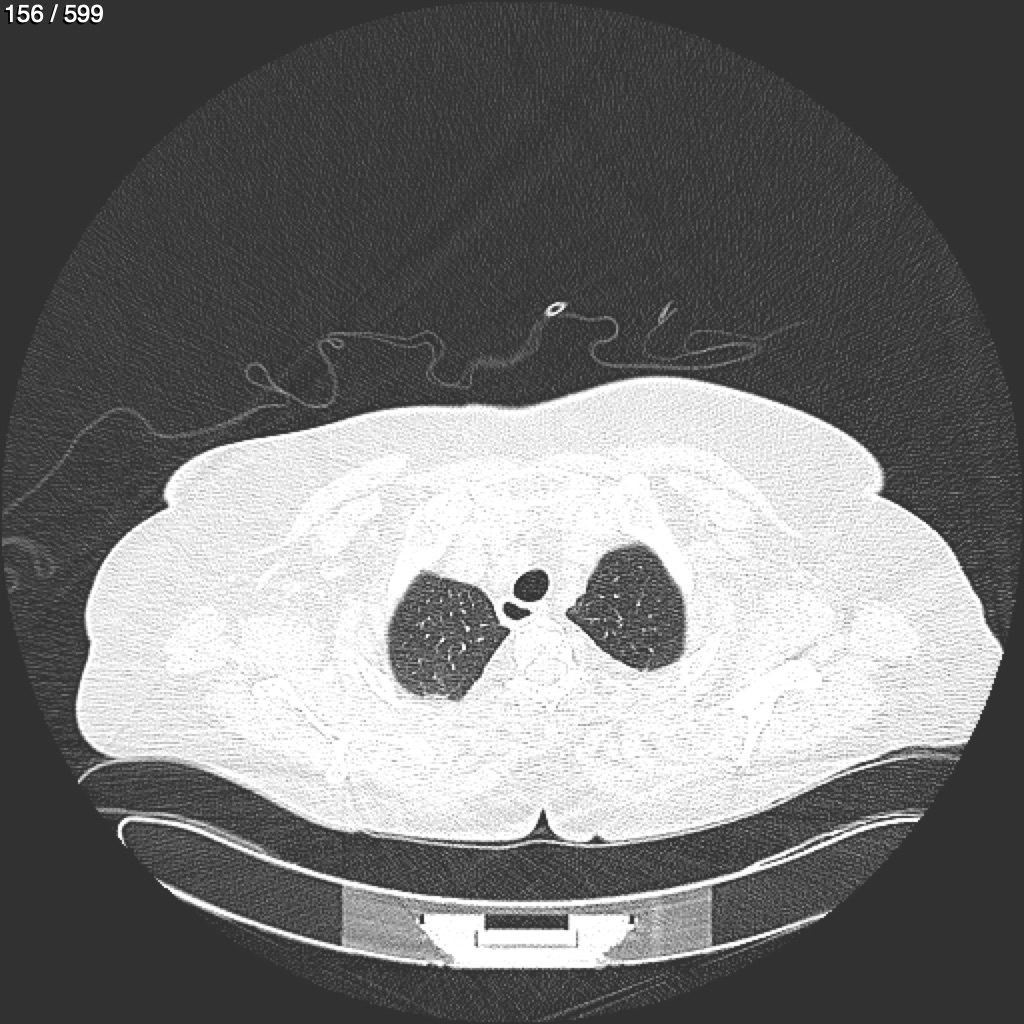

Home G​l​o​r​i​a​ ​G​l​a​d​y​s​ ​B​e​a​s​l​e​y​ ​-​ ​T​ó​r​a​x​ ​T​o​r​a​x​_​S​i​m​p​l​e​ ​(​A​d​u​l​t​o​)